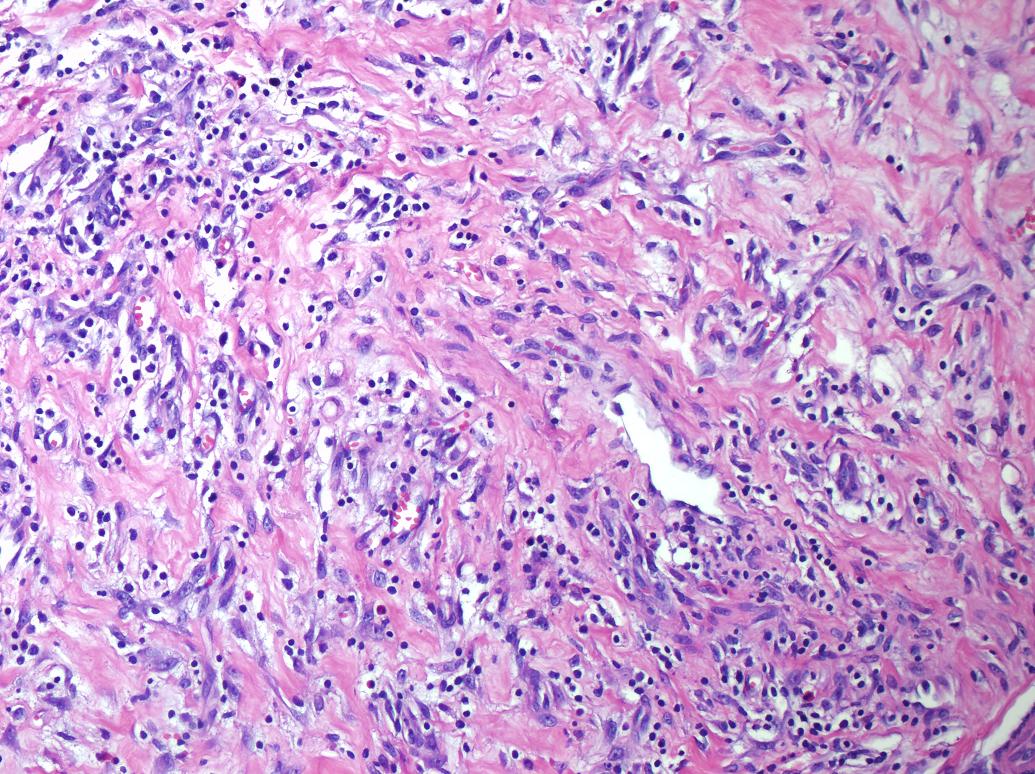

Cervical Lymphadenitis Due to Nodular Fasciitis in a Child

Nodular fasciitis is a benign, reactive proliferation of fibroblasts in the subcutaneous tissues. It usually affects the trunk and upper extremities, and rarely the head and neck region of young adults. It is rare among children and the histologic findings may incorrectly suggest malignant lesions. We describe a two-year-old girl that referred to our clinic with complaints of fever and swelling on the right side of neck and diagnosed as lymphadenitis clinically. Cervical lymphadenitis due to nodular fasciitis is a rarity. We emphasize that nodular fasciitis needs to be included in the differential diagnoses of neck lymphadenitis during childhood.